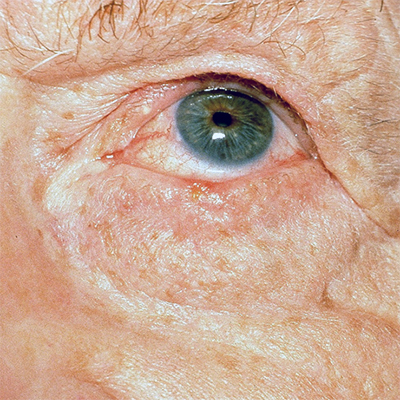

Basal Cell Carcinoma (BCC) Photos

Basal cell carcinoma on the posterior torso. Photo: International Skin Imaging Collaboration at isic-archive.com

Basal cell carcinoma on the neck. Photo: International Skin Imaging Collaboration at isic-archive.com

Basal cell carcinoma on the anterior torso. Photo: International Skin Imaging Collaboration at isic-archive.com

Basal cell carcinoma on the anterior torso. Photo: International Skin Imaging Collaboration at isic-archive.com

Basal cell carcinoma on the anterior torso. Photo: International Skin Imaging Collaboration at isic-archive.com

Basal cell carcinoma presenting as an open sore on the ear. Photo: International Skin Imaging Collaboration at isic-archive.com

Basal cell carcinoma presenting as a pink growth. Photo: International Skin Imaging Collaboration at isic-archive.com

Basal cell carcinoma on the leg. Photo: International Skin Imaging Collaboration at isic-archive.com

A small pink growth with a slightly raised, rolled edge and a crusted indentation in the center. (BCC)